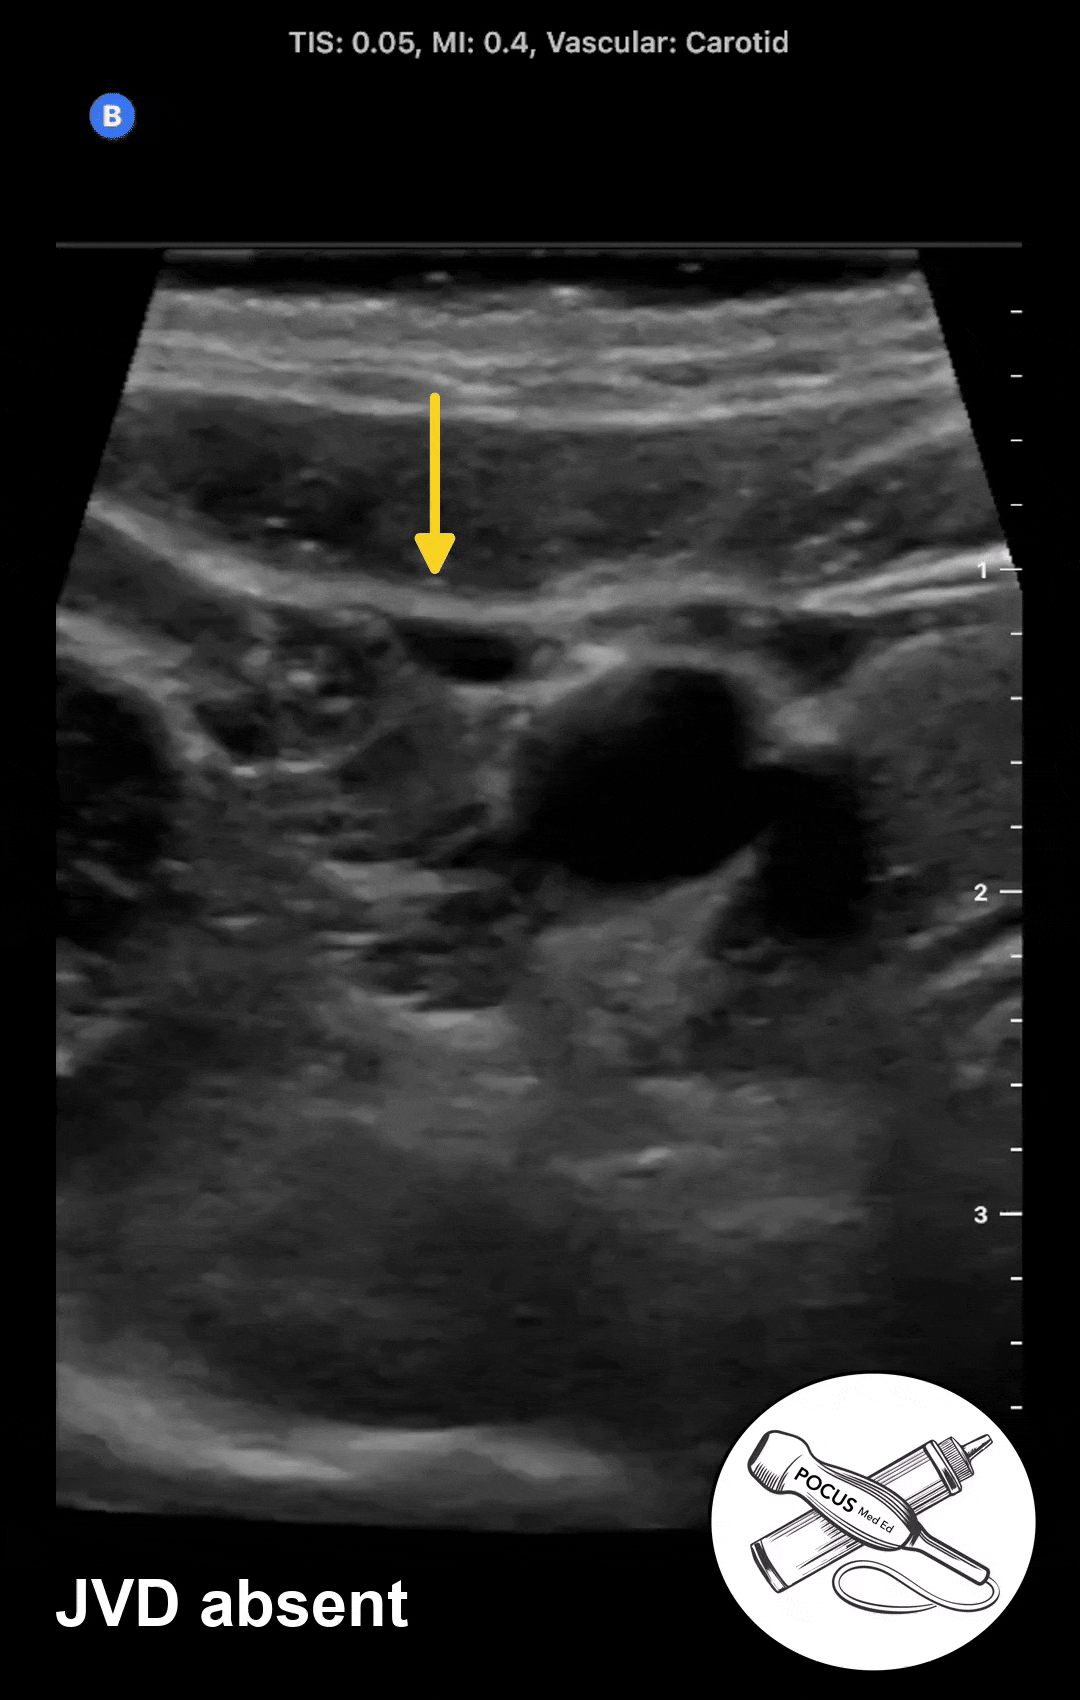

Step 1: Determine if JVD is present

At 45 degrees, in a patient with normal right atrial pressure and no JVD, the jugular vein should be fully or partially collapsed with regular respiration. Most jugular veins sit at the 10 or 12 o'clock position as seen in this example. When JVD is present, the POCUS exam will reveal the jugular vein that is distended without collapse during regular respiration.